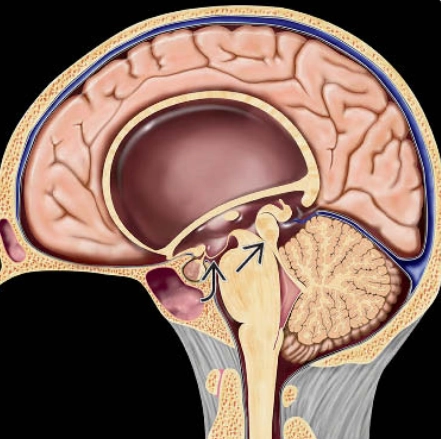

Não úng thủy tắc nghẽn ngoài não thất (EVOH - Extraventricular Obstructive Hydrocephalus)

16/03/2026